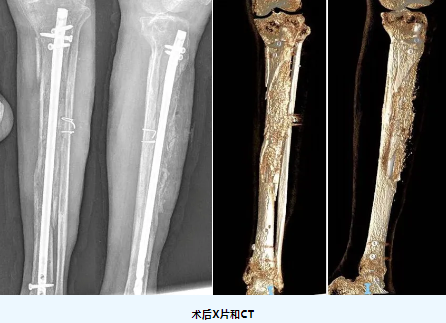

患者术后3个月再次入院,经创伤骨科副主任(主持工作)吴浩俊主任医师查看病人后,组织团队成员对该患者情况进行评估,最终决定对该患者实施了“外固定支架拆除、左胫骨骨水泥取出、胫骨骨折髓内钉内固定、自体骨和异体骨混合植入术”,现患者伤口愈合良好,肢体进行早期功能训练和康复治疗。